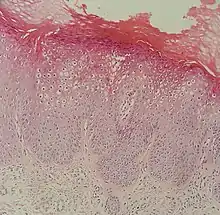

Flat warts, technically known as Verruca plana, are reddish-brown or flesh-colored, slightly raised, flat-surfaced, well-demarcated papule of 2 to 5 mm in diameter. Upon close inspection, these lesions have a surface that is "finely verrucous".[1][2] Most often, these lesions affect the hands, legs, or face, and a linear arrangement is not uncommon.[2] At histopathology, flat warts have cells with prominent perinuclear vacuolization around pyknotic, basophilic, centrally located nuclei that may be located in the granular layer.[3] These are referred to as "owl's eye cells."[3]

Micrograph of a flat wart